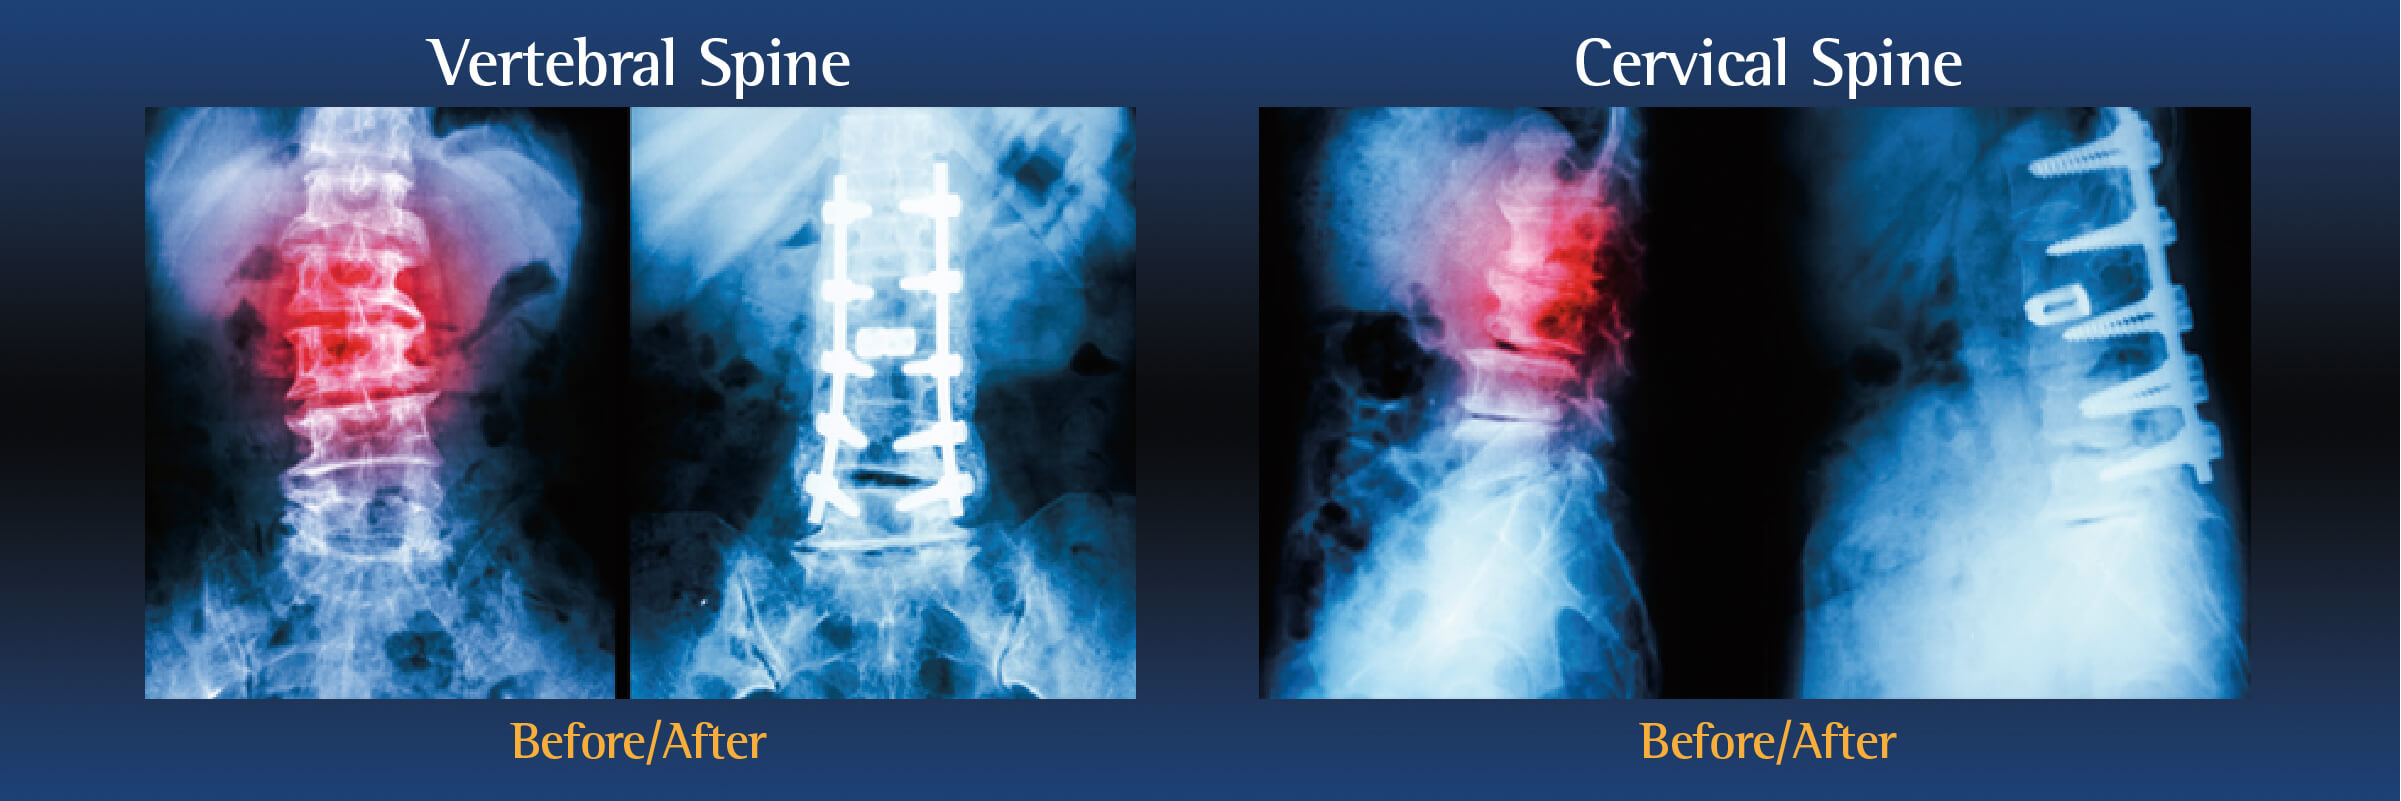

The goal of a spinal fusion is to join two or more vertebrae together using bone grafts to stabilize the spine and decrease pain. While spinal fusion limits the movement of those bones, it can sometimes increase your mobility as your pain is alleviated.

During the operation, an incision is made in the neck, back or abdomen. Bone, debris, bone growths, lamina, and/or the damaged vertebral disc may be cleared from the spine, creating more space and relieving pressure on the spinal nerves. The surgeon will then take the proper steps to correct the patient’s specific problem.

Bone grafts may then be placed in the space or along the side of the spine. If additional support is needed, metal hardware (including pins or screws), may be used to steady the spine as it fuses. The incision is closed to finalize the surgery.

The grafts will grow into solid bone, fusing together the vertebrae. Patients may have to wear a back brace post-surgery, which will support your spine and keep the vertebrae from moving as the grafts fuse together.